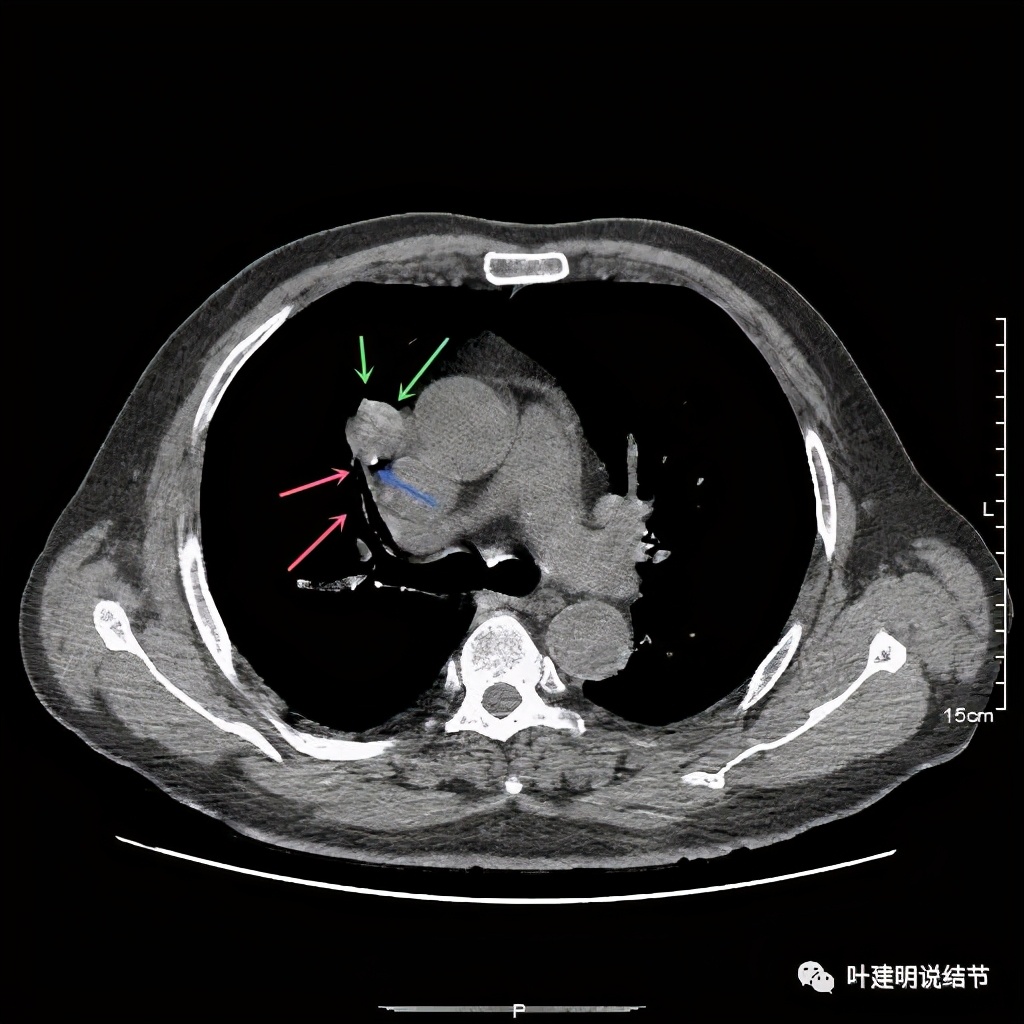

上图示病灶密度不均,但边缘过于光滑(绿色);支气管似有截断(粉色);局部有点状钙化(蓝色)

上图也示病灶密度不均,但边缘过于光滑(绿色);支气管似有截断(粉色);局部有点状钙化(蓝色)